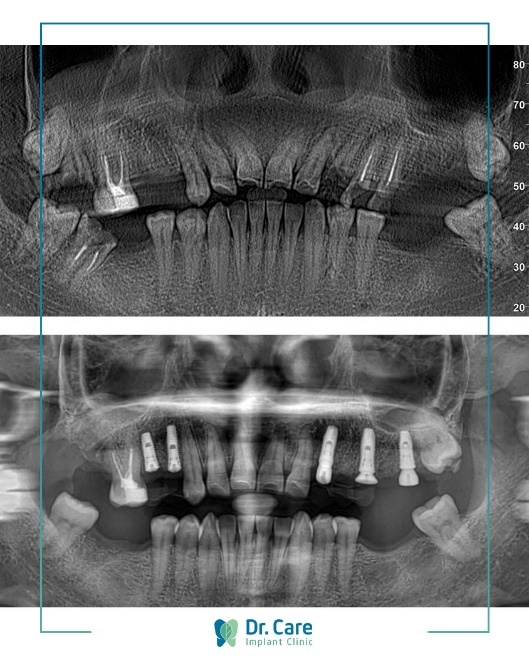

Hình ảnh trước và sau khi trồng răng Implant của chị Kim Loan